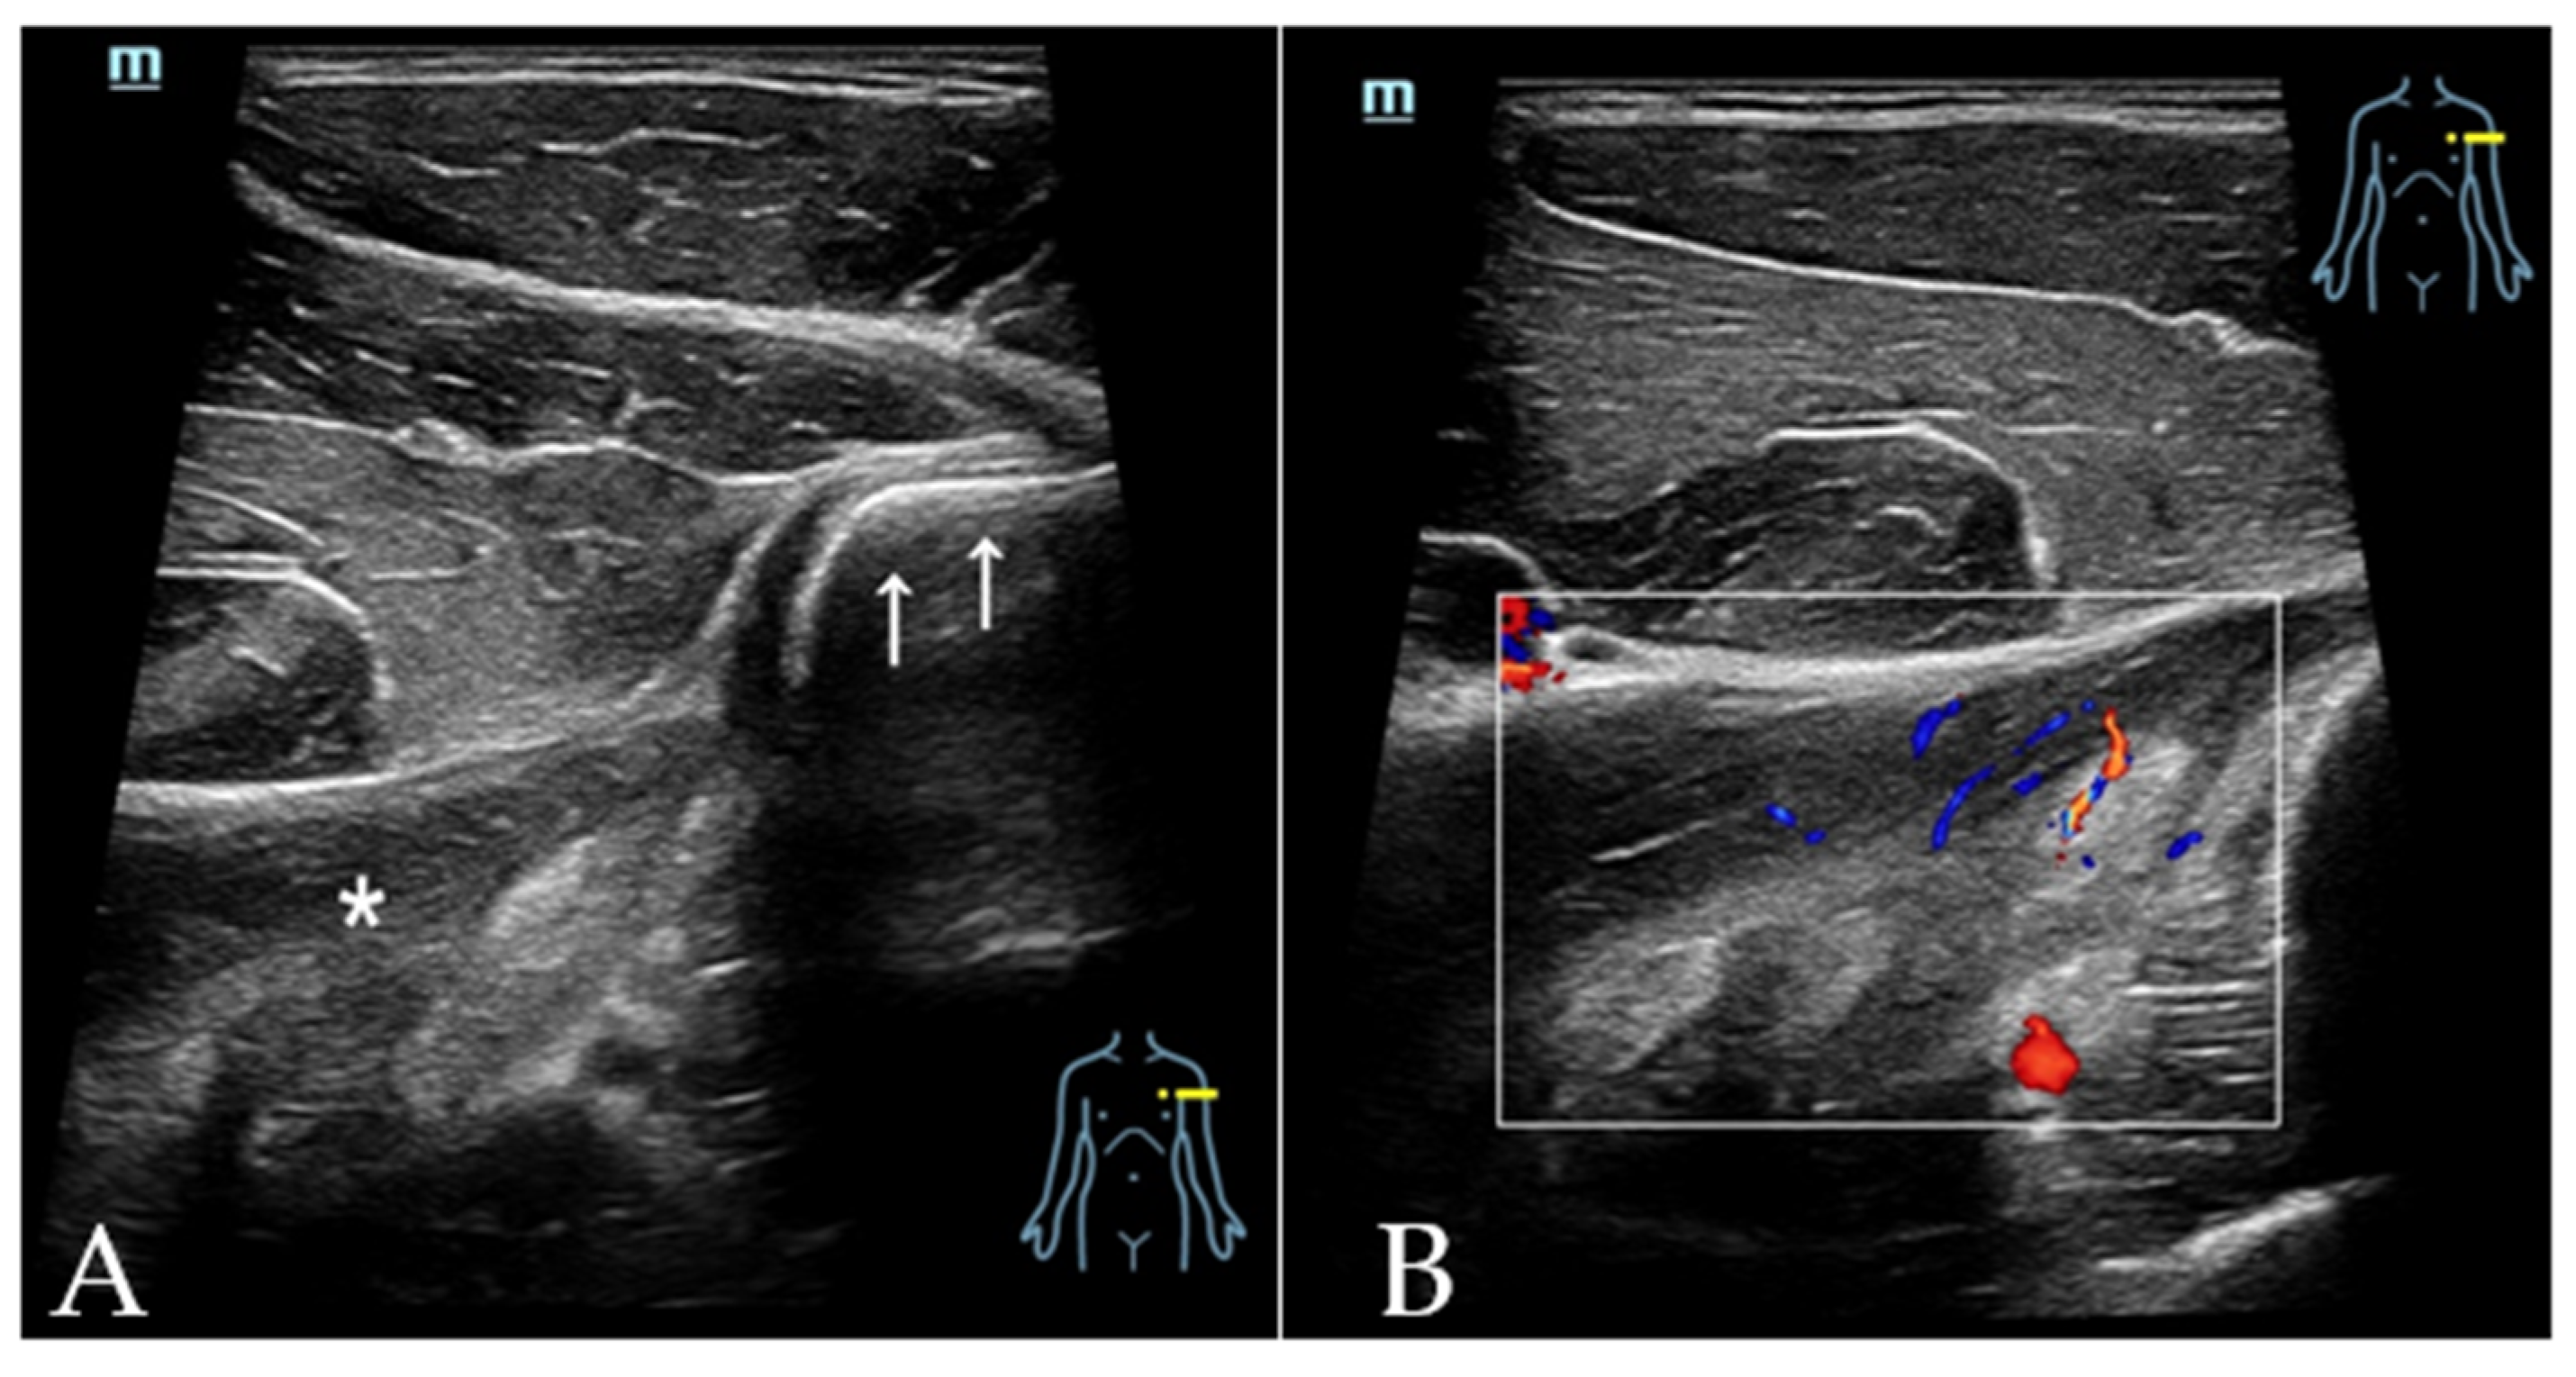

4.5. Injuries to the LD and TM